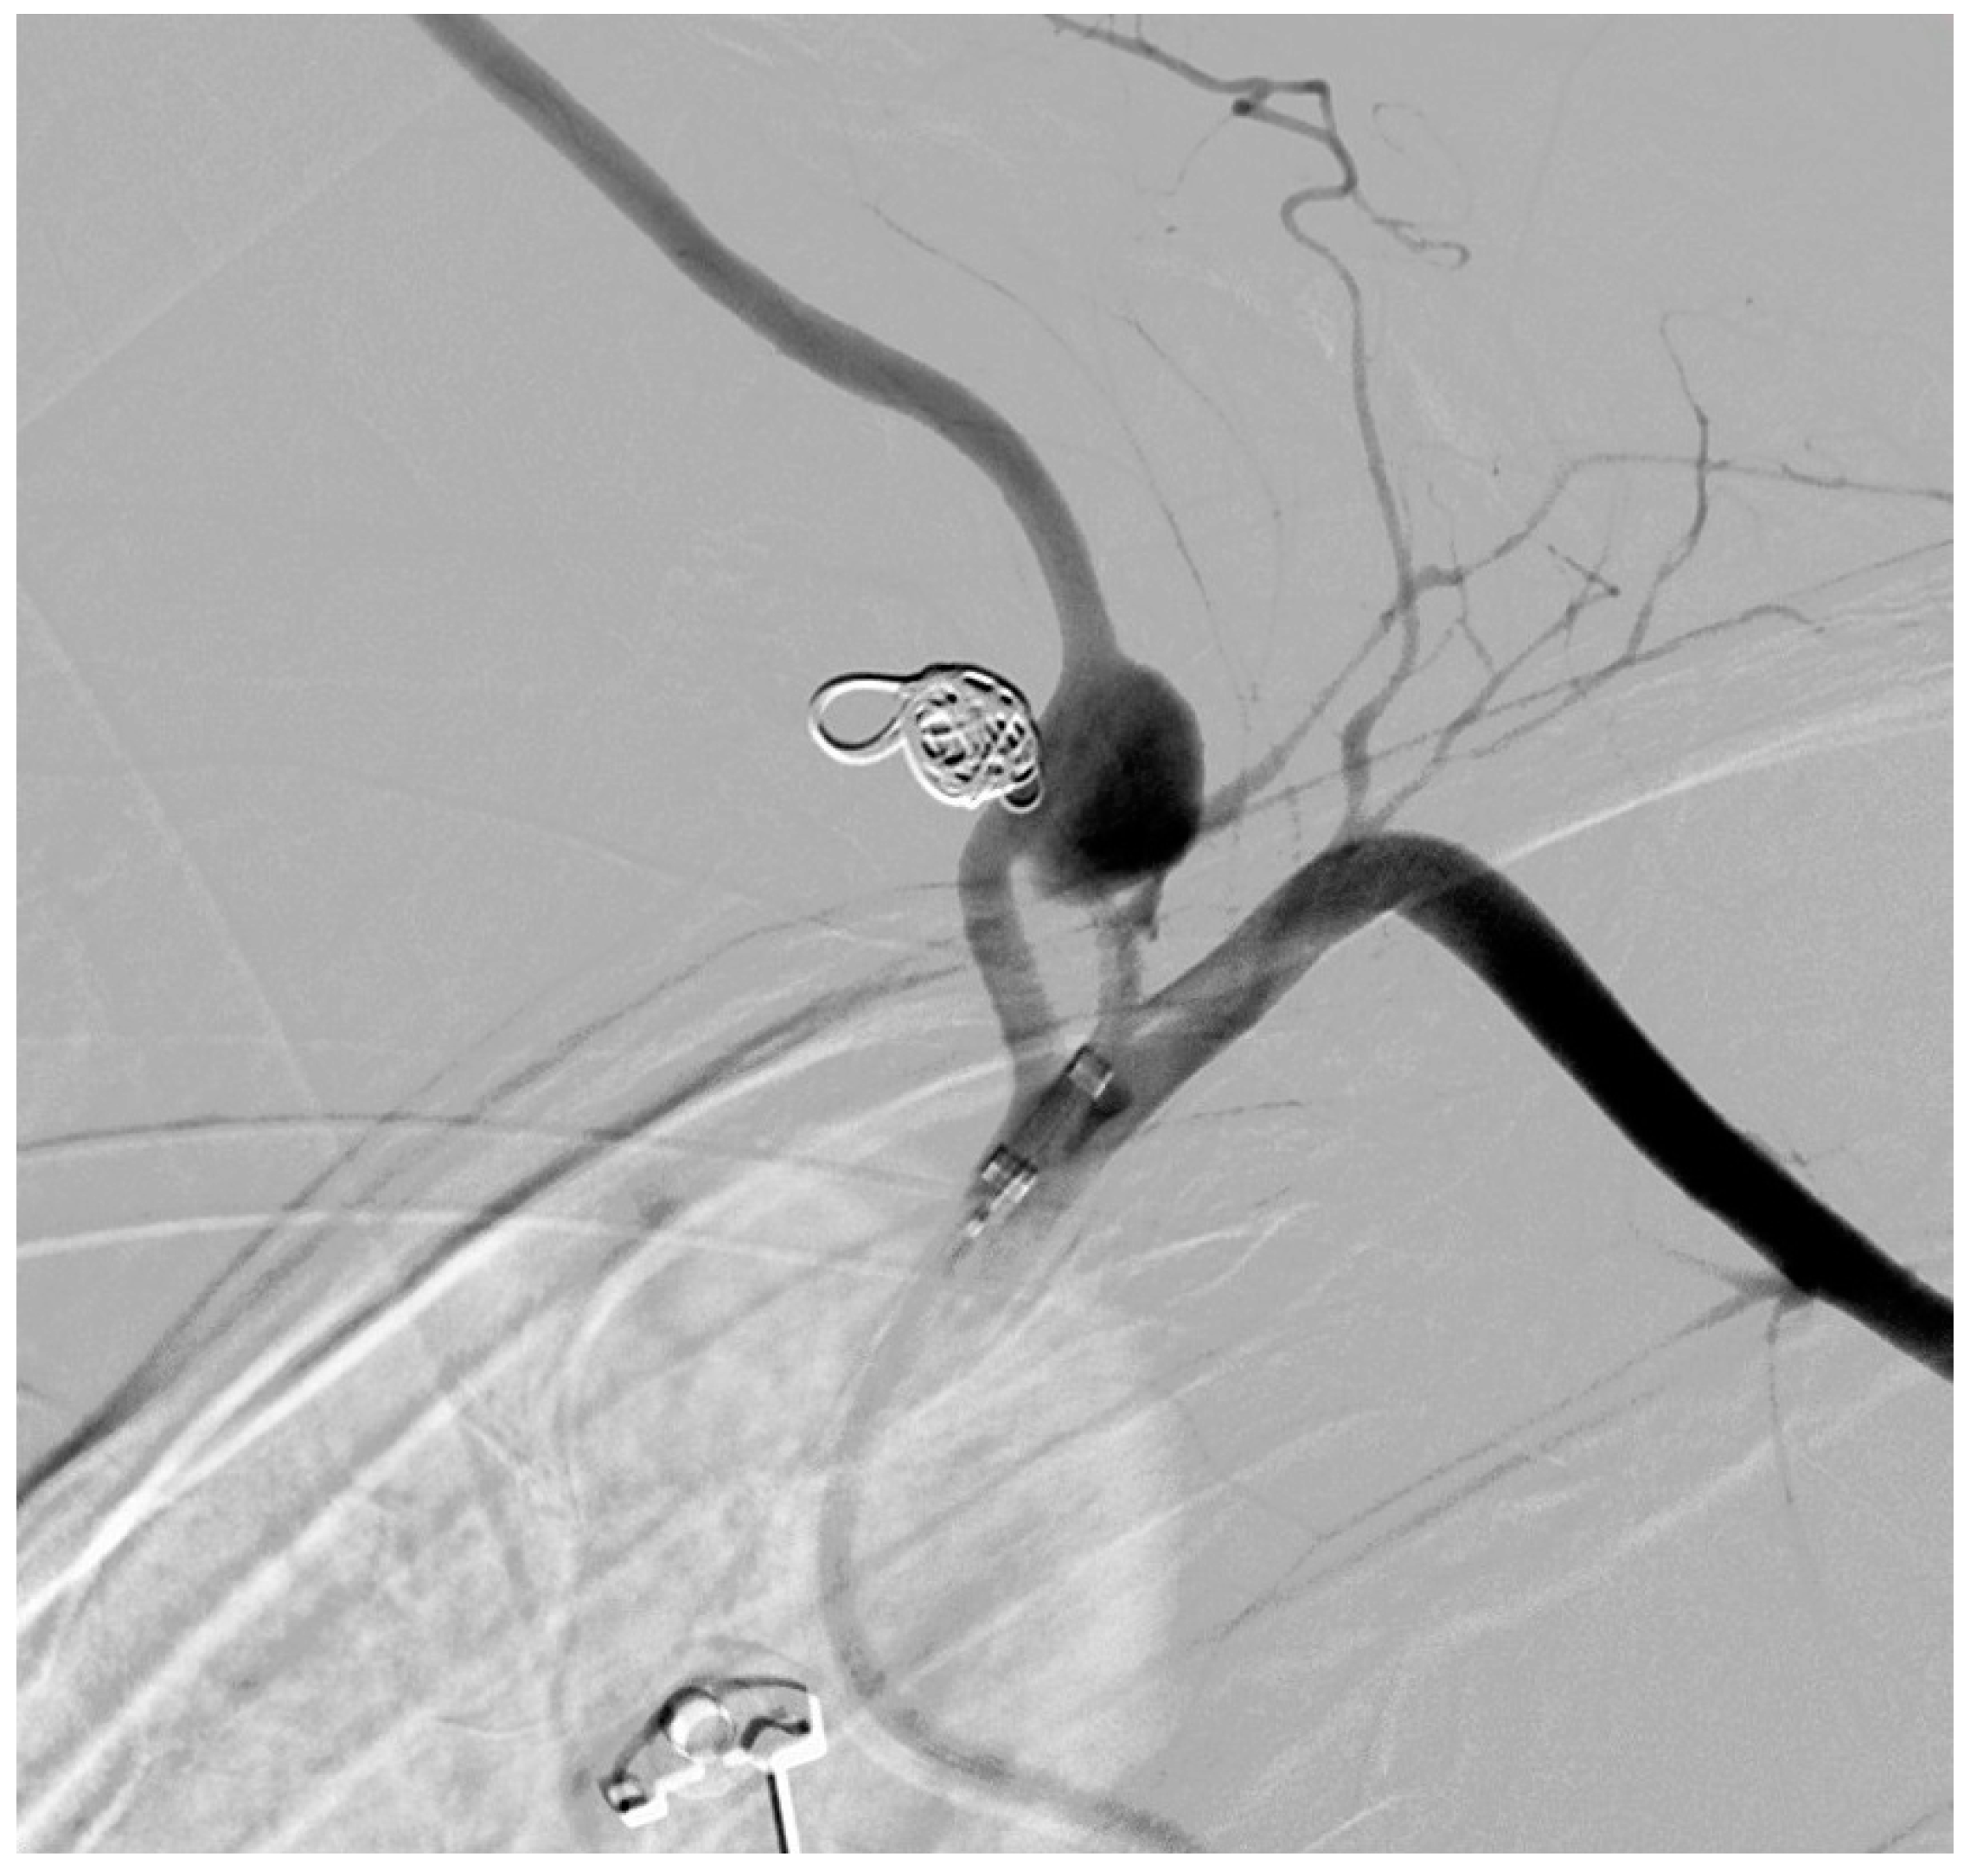

Successful Management of Thyrocervical Trunk Aneurysm Ruptured into the Thoracic Cavity After Cesarean Section in Nonstable Patient with Neurofibromatosis Type I

2. Case Description